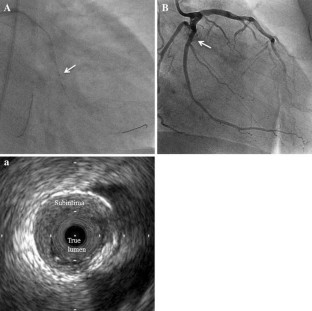

We describe an initial clinical chronic total occlusion (CTO) case in which CTO-specific intravascular ultrasound (IVUS): Navifocus WR was useful for navigating the second guidewire into the true lumen under the IVUS observation from the subintimal space.

Fig. 3